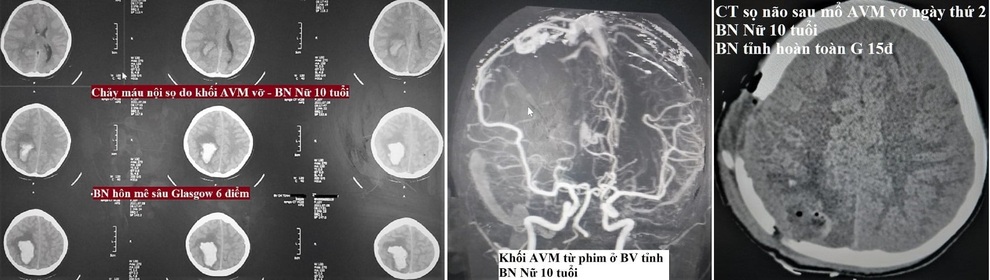

Hình ảnh chảy máu não của bệnh nhi.

Trước đó, bệnh nhi được đưa đến Bệnh viện tỉnh Phú Thọ vì chảy máu nội sọ do dị dạng động tĩnh mạch bị vỡ, và được chuyển ngay lên tuyến trên.

Tiếp nhận bệnh nhi trong tình trạng nguy kịch, toàn bộ ê kíp Trung tâm Đột quỵ và Khoa Phẫu thuật thần kinh hội chẩn nhanh chóng điều trị. Bệnh nhi được phẫu thuật cấp cứu. Sau ca phẫu thuật hết tác dụng của thuốc gây mê, bệnh nhi tỉnh lại, giao tiếp tốt.